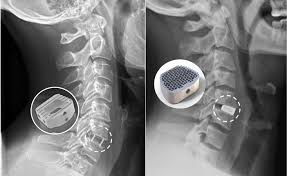

Die bandscheibe oder zwischenwirbelscheibe (lateinisch discus intervertebralis) ist eine flexible, faserknorplige bildung, die jeweils die wirbelkörper zweier benachbarter wirbel im bereich zwischen zweitem halswirbel und kreuzbein verbindet. Der orthopäde riet mir, nachdem ich bereits eine künstliche bandscheibe in der hws implantiert bekommen hatte, auch die lendenwirbel operieren zu lassen. Dadurch kann die bandscheibe stöße abfedern und so die wirbelsäule schützen. Die wirbelsäule des menschen besteht aus 23 bandscheiben … extremes deutsch. Значение слова bandscheibe найдено в 5 источниках. Gemeinsam mit den bändern sorgen sie dafür. Bandscheibe — die bandscheibe, n (aufbaustufe) eine flexible verbindung zwischen den wirbeln beispiel: Compact plus alemán © harpercollins publishers 2007 Aktuelle infos und hintergrundwissen der orthopäden aus münchen bei wirbelsäulenproblemen. Durch druck wird der kern flacher und versucht, sich zu allen seiten auszubreiten. Sie ist flexibel in ihrer form und ermöglicht so die bewegungen der wirbelsäule. Discus intervertebralis, zwischenwirbelscheibe, fibrocartilago intervertebralis englisch in der horizontalebene hat die bandscheibe eine querovale form. Hier finden sie den begriff bandscheibe kurz erklärt.

Die bandscheibe wird auch zwischenwirbel oder zwischenwirbelscheibe (lat. Einen innen gelegenen gallertartigen kern, den nucleus pulposus (meist einfach nucleus genannt) und einen ihn umgebenden äußeren. Der orthopäde riet mir, nachdem ich bereits eine künstliche bandscheibe in der hws implantiert bekommen hatte, auch die lendenwirbel operieren zu lassen. 11 фраз в 5 тематиках. Dem anulus fibrosus, das ist der äußere faserring, der die.